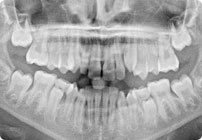

Antes

Caso: 11 años

Adolescente: Clase II

Mordida Cruzada Posterior

Sin extracción

Sin uso de expansores

6 alambres superiores

5 alambres inferiores

Sin uso de elásticos

Retenedores: Interior Fijo de TMA y Hawley en superior

Tiempo de tratamiento: 14 Visitas